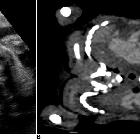

Antenatal ultrasound

Thus identification of a dividing membrane or two placentas excludes the diagnosis. Definitive sonographic features will depend on the type of fusion.

General features include:

- lack of a separating inter-twin membrane

- non-separable skin contours with an inability to separate the fetal bodies

- detection of other anomalies in a twin gestation

- solitary umbilical cord with more than 3 vessels present

- both fetal heads persistently at the same level

- backward flexion of the cervical spine (due to the fact that most conjoined twins are fused ventrally and face each other

- bibreech or less commonly, bicephalic presentation

- constant relative fetal positions